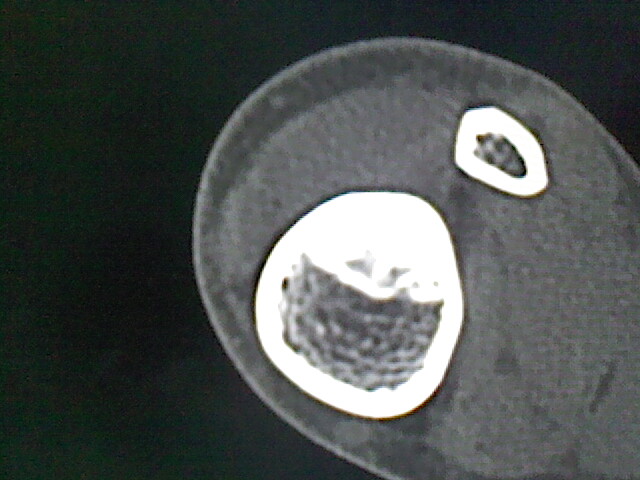

男,33岁,外伤后拍片发现,左侧胫骨可见一高密度影

考虑,右胫骨下端内生性骨瘤。

考虑右胫骨下端内生性骨瘤。

内生软骨瘤可能

骨样骨瘤。

可见瘤巢,考虑骨样骨瘤

内生骨瘤可能性大,不知病人有何症状,不除外骨样骨瘤

良性骨肿瘤,以内生软骨瘤或骨纤维瘤可能大。请上传骨窗。